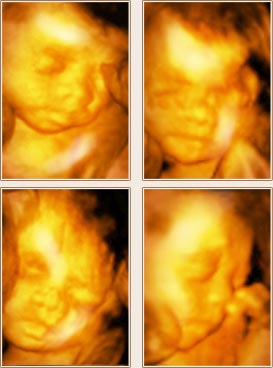

四四维彩超宝宝照片

点击预约>>

- 出生前100天

- 出生后100天

- 在检查的同时,美国GE-E8四维彩超利用四维成像技术(4D),直观、立体地显示人体器官的三维结构及动态、实时地观察立体结构,高清显示腹中宝宝的实时动态“动画”,记录宝宝的一举一动,并可刻录成高清视频光盘留念。这不仅是独一无二的孕期纪念,也是送给未来宝宝的珍贵礼物。